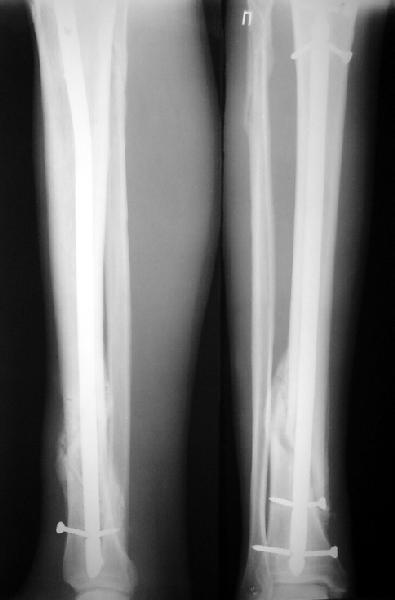

По крайней мере ходящих без дополнительной опоры через 1 месяц после операции с небольшой - при изолированной травме немало. Нестабильные по оси, кстати, не только оскольчатые, но и спиральные.

И если пациент еще не возвращается к полной нагрузке и функции, то не потому, что не разрешает врач, опасаясь несостоятельности фиксации.

Как мне показать пример? Фото стоящего на одной оперированной конечности пациента? O! Пример, подвигнувший нас на некоторое изменение технологий. Пациент этот ходил с полной нагрузкой вопреки рекомендациям. В качестве подтверждения - сломанный проксимальный статический винт к 1 мес., а к 2 мес. - все остальные. Сейчас мы перешли на более fool-proof остесинтез.

На мой взгляд, на снимках, приведённых Вами - неправильно сростающийся перелом дистальной трети большеберцовой кости, состояние после остеосинтеза интрамедуллярным гвоздём.

Как Вы пишите снимок под номером 1 - менсяц после операции, под номером 2- два месяца после операции.

Вы не послали послеоперационный снимок, поэтому трудно судить о состоянии редукции после операции.

Установка с медиальной стороны гвоздя в области дистального фрагмента дополнительного шурупа помогло бы Вам репонировать и удержать перелом в анатомическом положении, предотвратило варусную деформацию и смещение по ширине.

I think that the X-Rays show S/P IMN of Spiral # of the Distal Tibia consoles in misalignment.

You wrote that a picture number 1 - f month after the surgery, and number 2-two months after the surgery.

You have not sent a postoperative X-Rays; so it's impossible to discuss about the condition of a reduction after operation.

Let to express concerning technique of operation my opinion... Insertion of a screw to medial side of a nail in distal fragment would help you to reduction and to keep this fracture in anatomic position has prevented varus deformity and displacement on width. By the way, if it is possible send a postoperative picture.